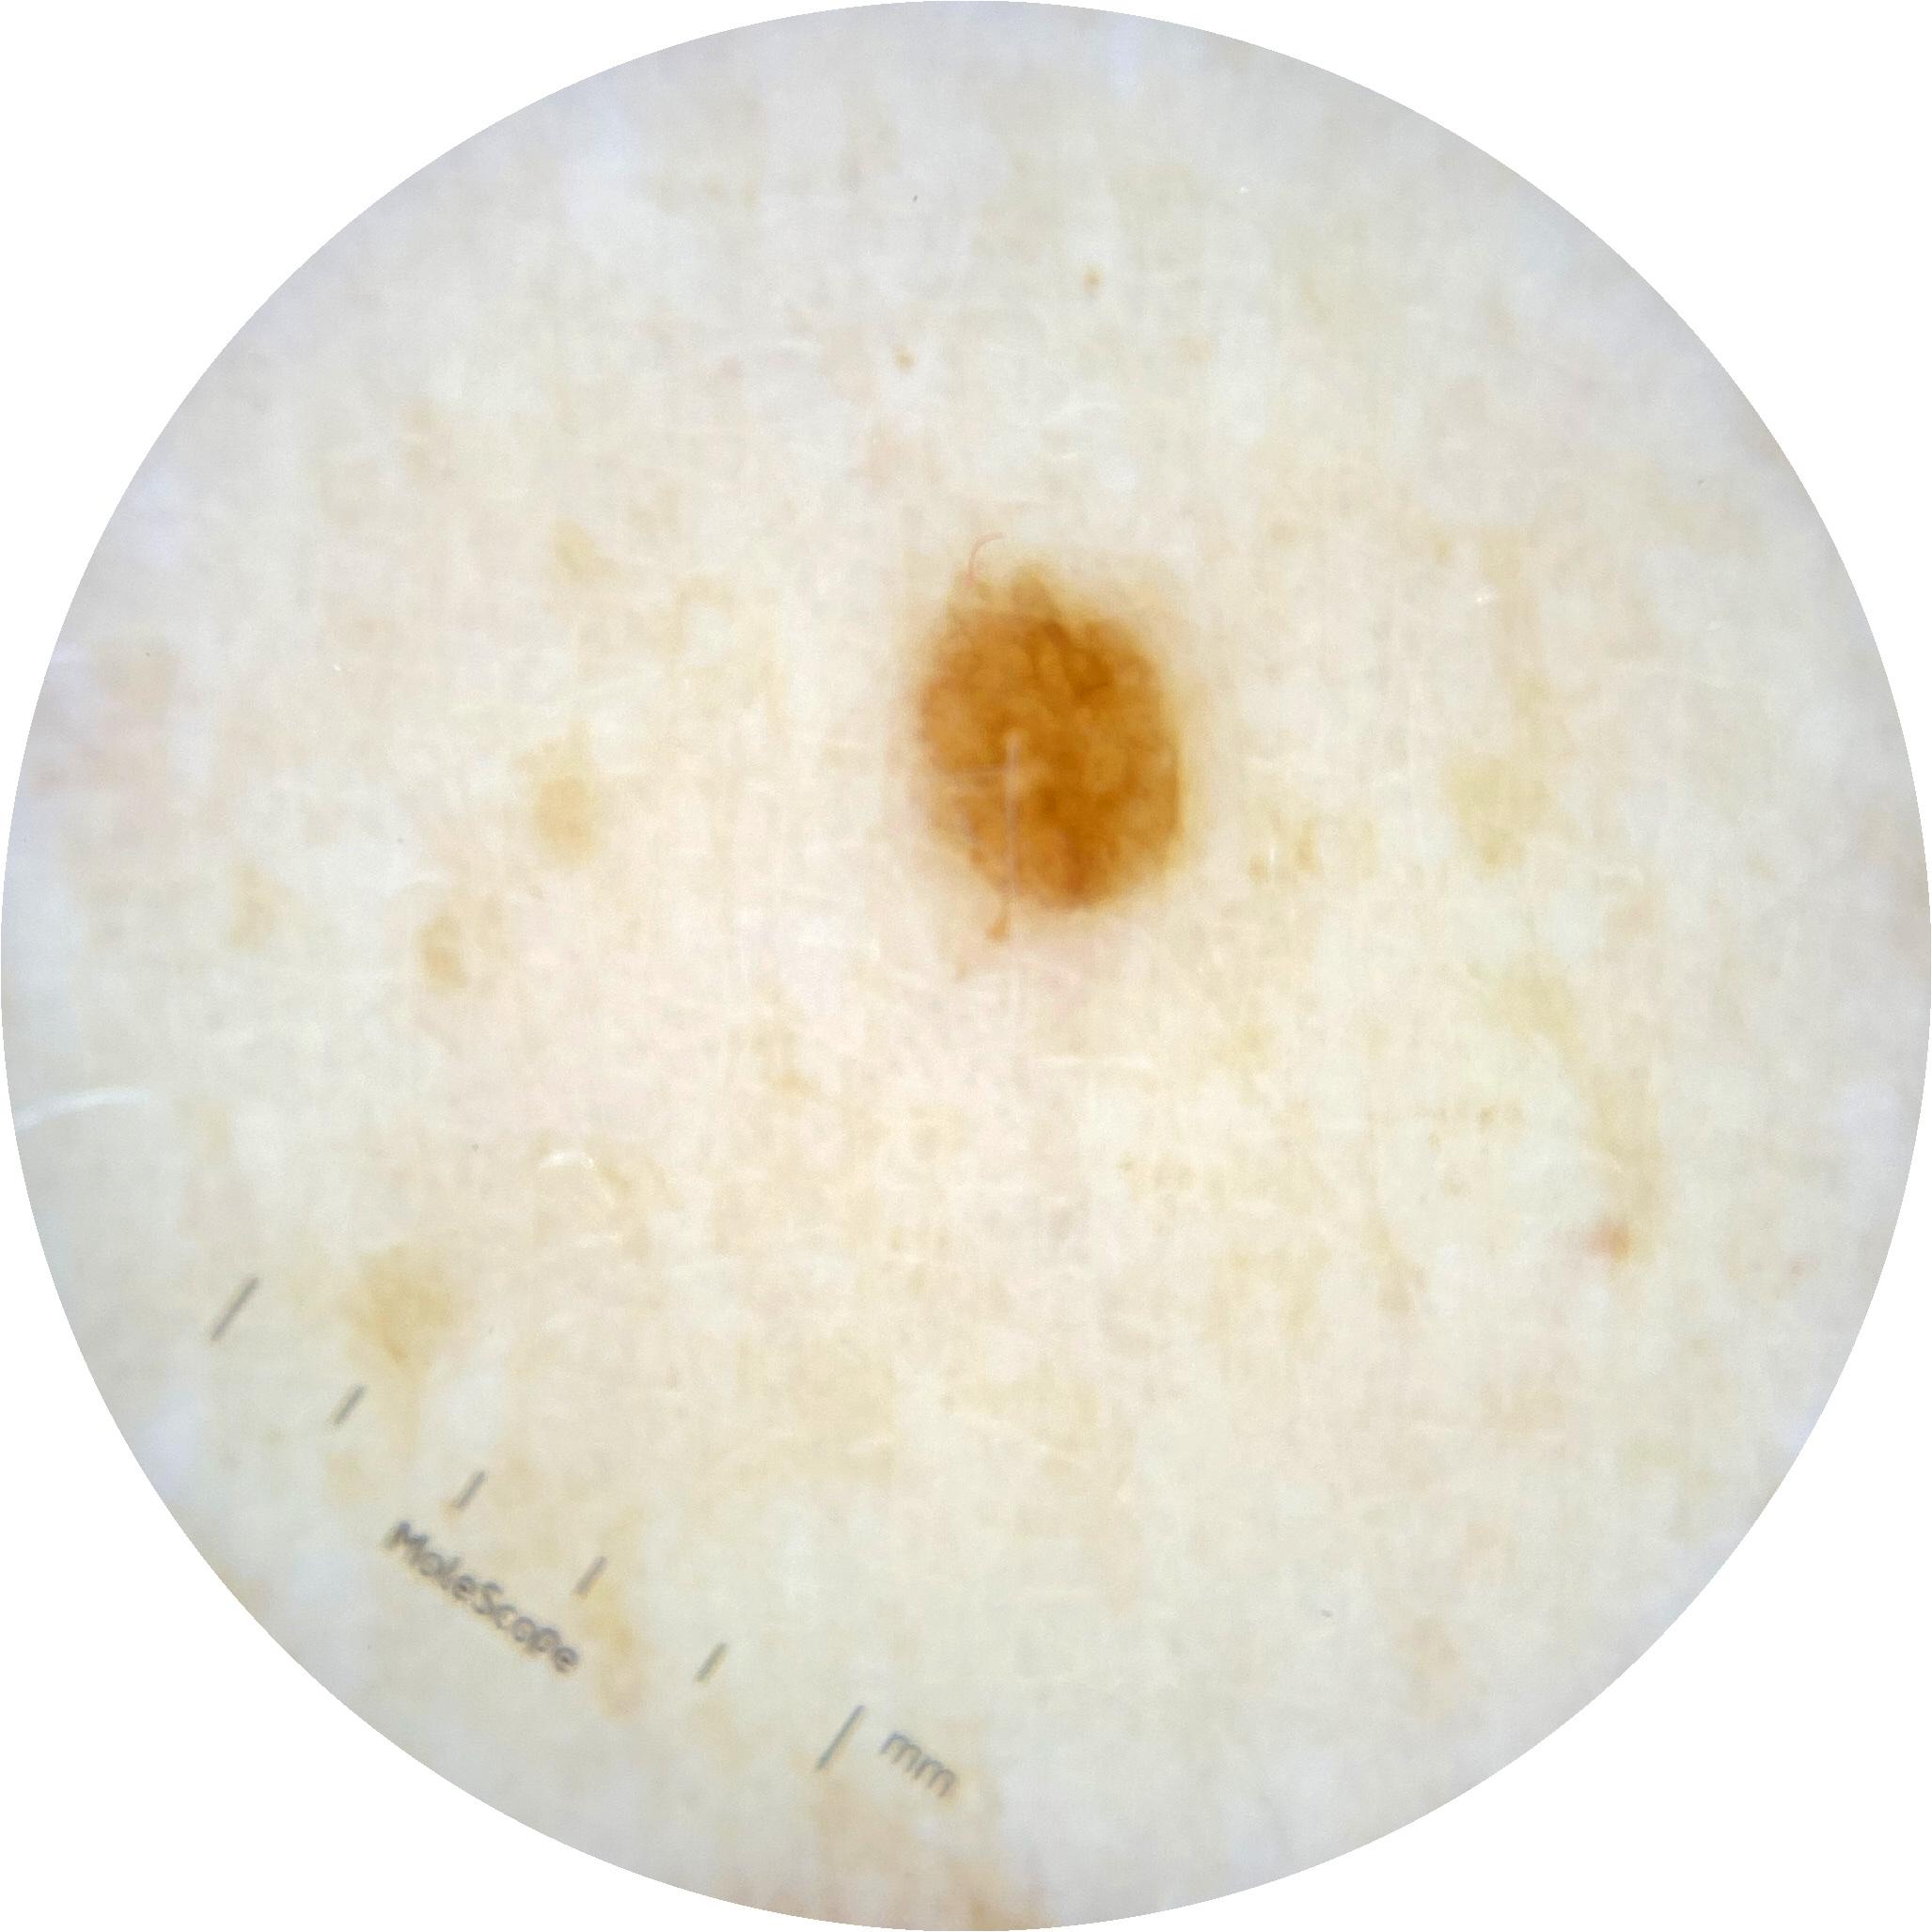

ISIC_2261268

acquisition_day 307

age_approx 50

anatom_site_1 Trunk

anatom_site_2 Posterior trunk

anatom_site_general posterior torso

diagnosis_1 Benign

diagnosis_confirm_type single image expert consensus

image_type dermoscopic